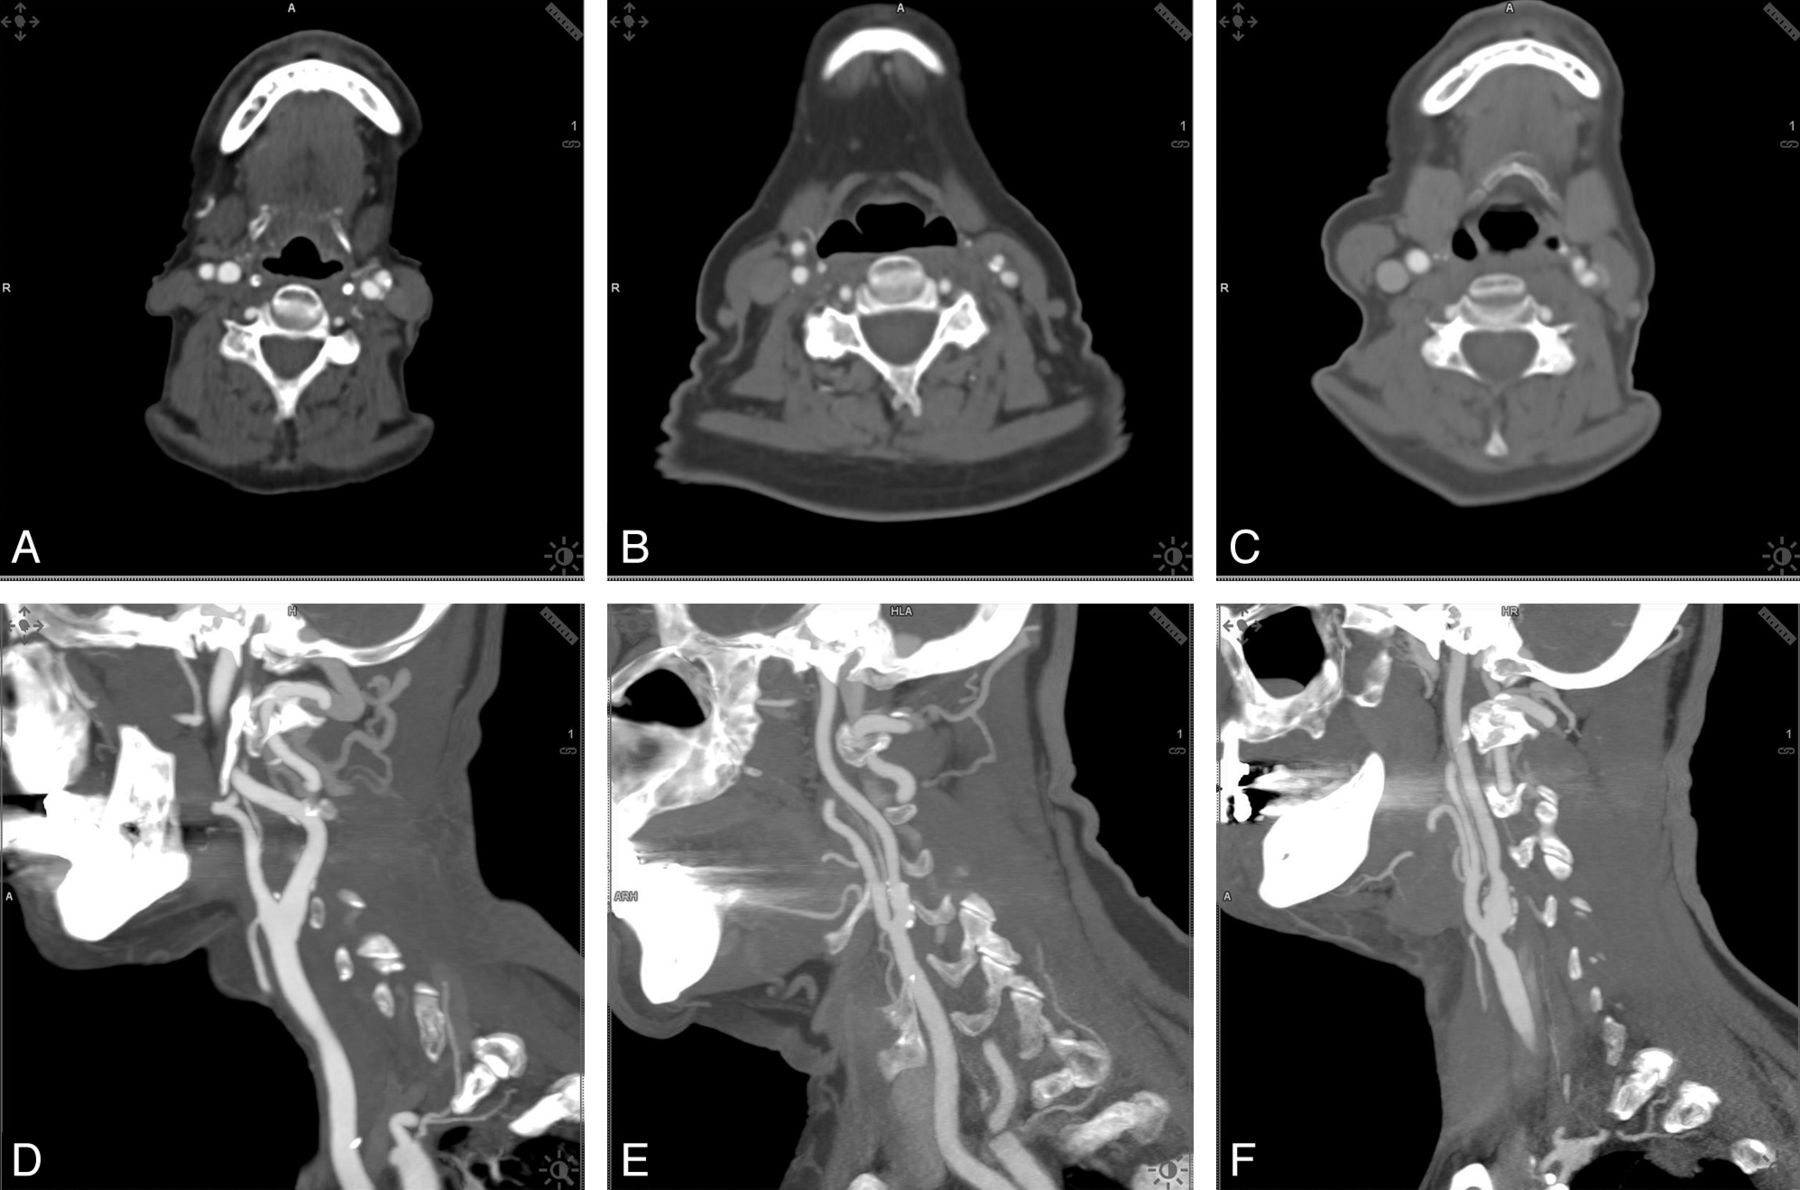

Examples of the different kilovolt groups, comparing examinations by use of 80, 100, and 120 kV in the axial plane and sagittal maximum intension projections are shown in Fig 1.

Examples of the different kilovolt groups. Comparison of examinations by use of 80, 100, and 120 kV in the axial plane and sagittal maximum intension projections.